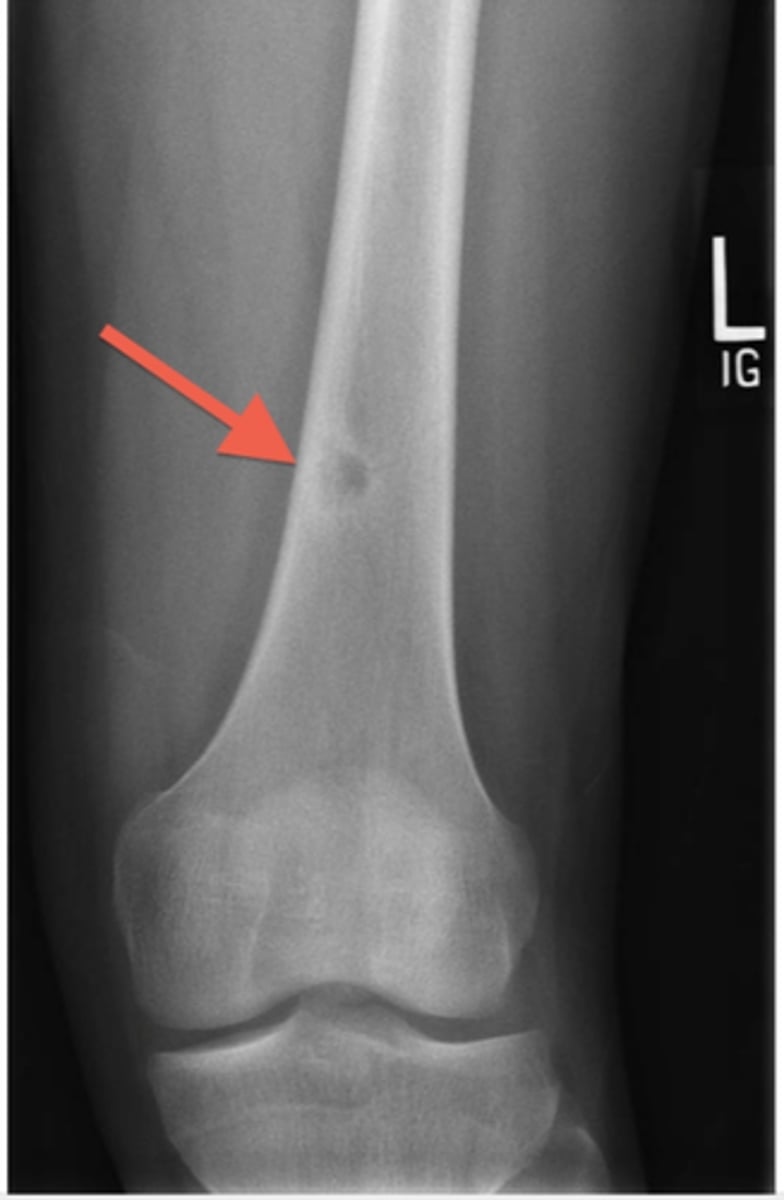

Osteosarcoma

Ewing sarcoma

X ray shows an osteolytic lesion with a periosteal reaction that produces layers of reactive bone, giving the classic onion skin appearance